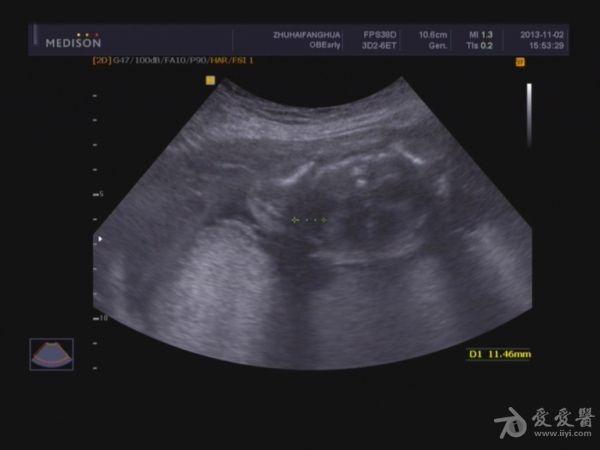

单胎妊娠;臀位,颅骨环基本完整,脑中线居中,CER: 24mm,CM:不清,双侧丘脑可见,侧脑室未见明显扩张,小脑可显示欠清,胎儿颈项部欠清,胎儿颜面显示不清,胸腔增大内见积液,腹壁完整,肝、可见,腹腔内大量积液,最大径约:71mm,胸腔内积液最大径:11.4mm,胃及膀胱显示不清。双肾显示不清。双侧四肢长骨显示欠清。

脐带:结构正常,脐动脉血流参数:SPV:33cm/s,PI:1.0,RI:0.62,S/D:2.6。典型图片如下: